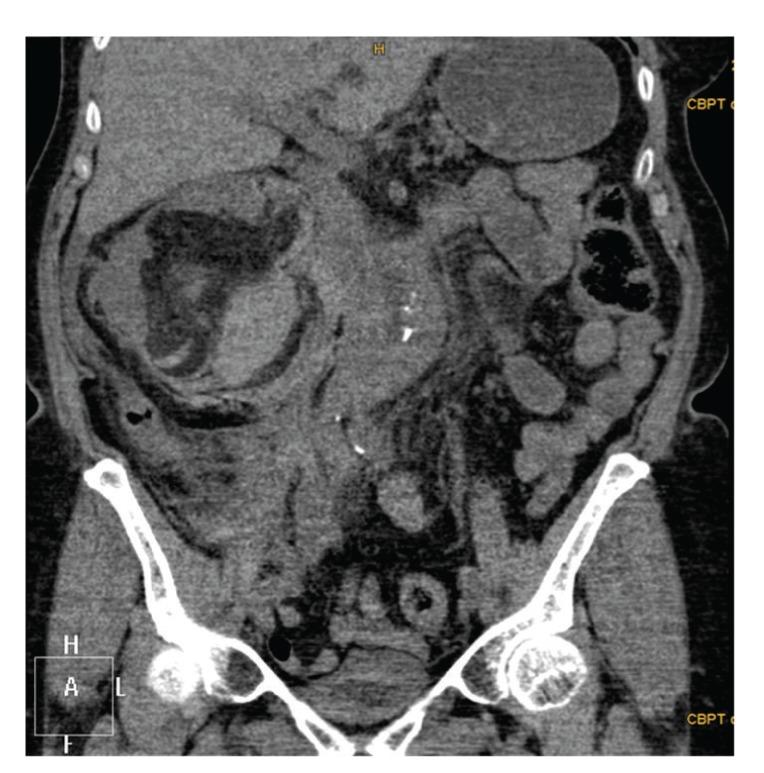

Spontaneous, nontraumatic retroperitoneal hemorrhage or Wunderlich syndrome (WS) is a rare but potential life-threatening condition. In most patients a bleeding renal neoplasm is the cause of the retroperitoneal hematoma. The management of this condition includes a conservative approach in the hemodynamically stable patients and active treatment in the unstable patients. Active treatment includes angioembolization or surgery. If angioembolization is not available open surgery is in most cases the preferred approach. We present a patient with a spontaneously ruptured kidney due to a central renal angiomyolipoma, which was treated by laparoscopic nephrectomy.

自发性、非创伤性腹膜后出血或温德利希综合征(WS)是一种罕见但可能危及生命的疾病。在大多数患者中,出血性肾肿瘤是腹膜后血肿的病因。这种疾病的治疗包括对血流动力学稳定的患者采取保守治疗方法,对不稳定的患者采取积极治疗。积极治疗包括血管栓塞或手术。如果无法进行血管栓塞,在大多数情况下开放手术是首选方法。我们报告一例因肾中心血管平滑肌脂肪瘤导致自发性肾破裂的患者,该患者接受了腹腔镜肾切除术。